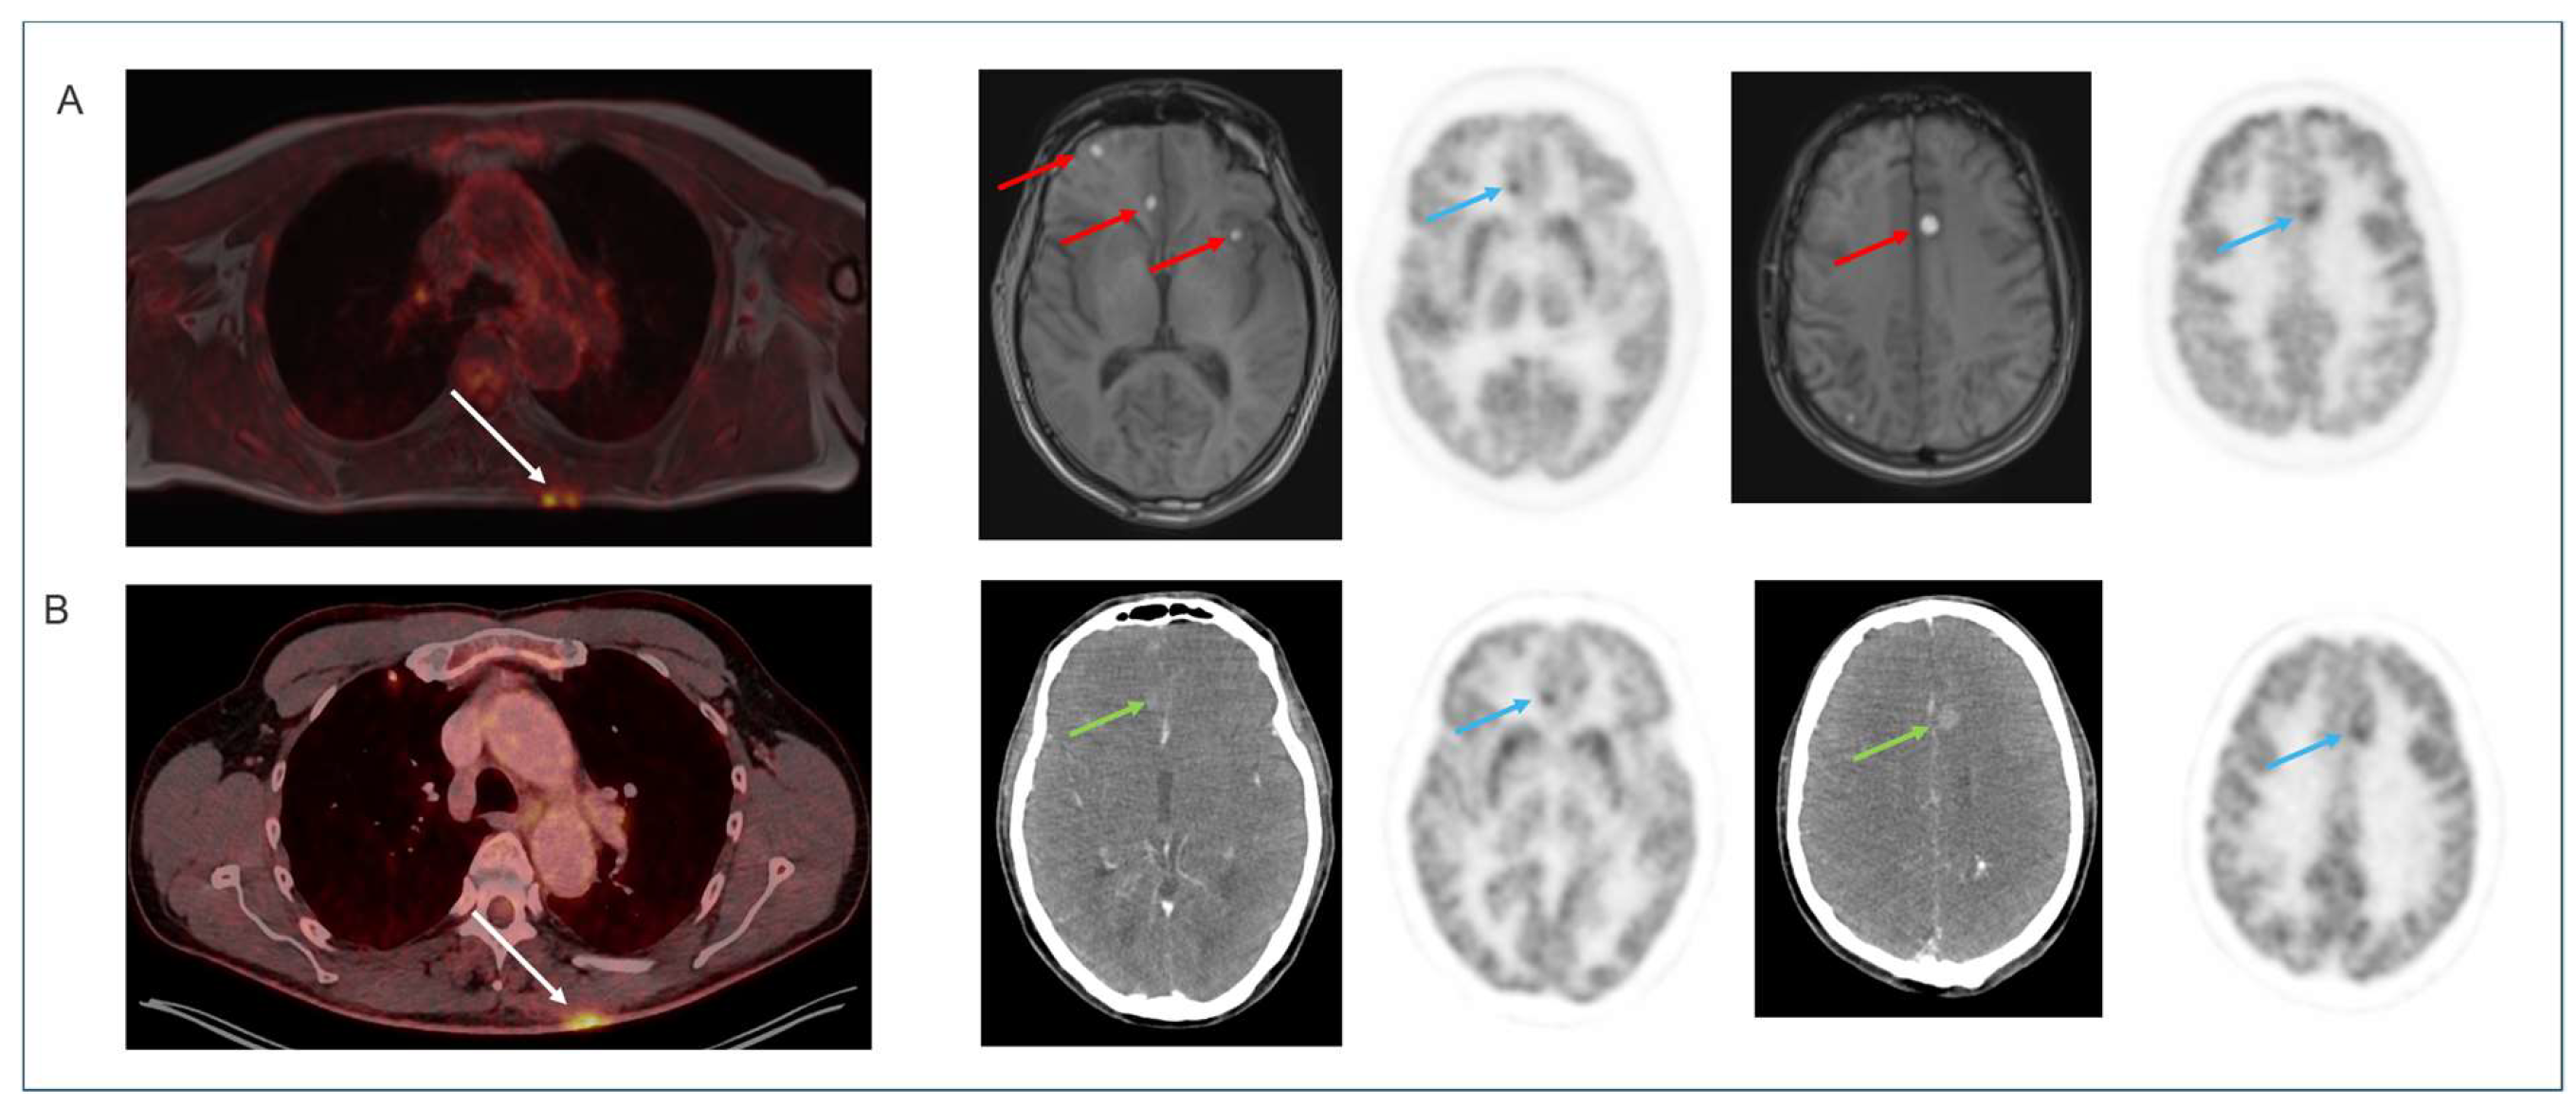

4.4. Non-Brain [18F]FDG Oncology Applications

- Ladefoged, C.N.; Andersen, F.L.; Andersen, T.L.; Anderberg, L.; Engkebolle, C.; Madsen, K.; Hojgaard, L.; Henriksen, O.M.; Law, I. DeepDixon synthetic CT for [18F]FET PET/MRI attenuation correction of post-surgery glioma patients with metal implants. Front. Neurosci. 2023, 17, 1142383. [Google Scholar] [CrossRef]

- Biondetti, P.; Vangel, M.G.; Lahoud, R.M.; Furtado, F.S.; Rosen, B.R.; Groshar, D.; Canamaque, L.G.; Umutlu, L.; Zhang, E.W.; Mahmood, U.; et al. PET/MRI assessment of lung nodules in primary abdominal malignancies: Sensitivity and outcome analysis. Eur. J. Nucl. Med. Mol. Imaging 2021, 48, 1976–1986. [Google Scholar] [CrossRef] [PubMed]